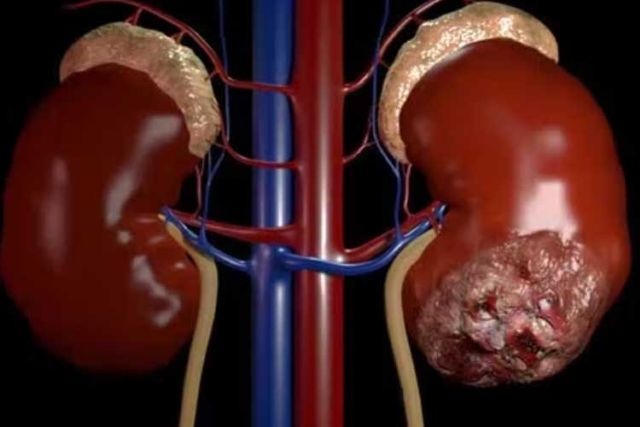

- Um dos principais desafios é o diagnóstico tardio, que torna o tratamento mais oneroso e menos eficaz — tanto para o paciente quanto para o SUS.